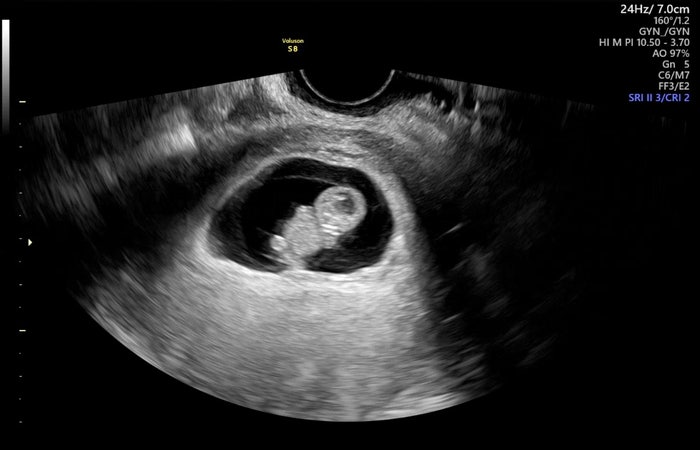

[9주차] 임신초기 증상과 젤리곰 초음파 사진, 입덧은 참을만하다

임신 9주차 초기 증상 : 입덧(먹덧과 체덧), 잦은 소변, 아랫배 당김, 가슴통증 처음 임산부석에 앉은 날, ...

[4주~8주차] 임신극초기증상과 함께 아기 천사가 찾아왔다

4주차~8주차 임신 극초기 증상 : 아랫배통증, 가슴통증, 미열, 출혈, 피고임, 입덧 9월 난임병원에서 검사...